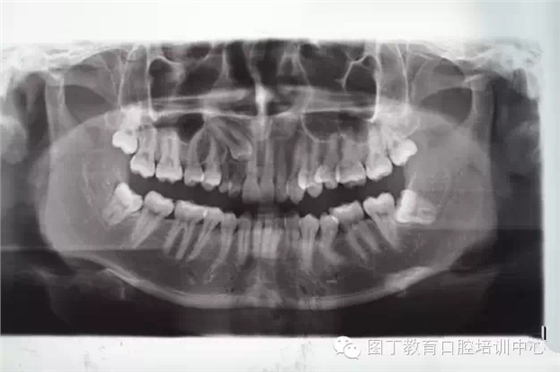

術前全景片檢查:13位于11、12根尖區(qū)。乳Ⅲ滯留。